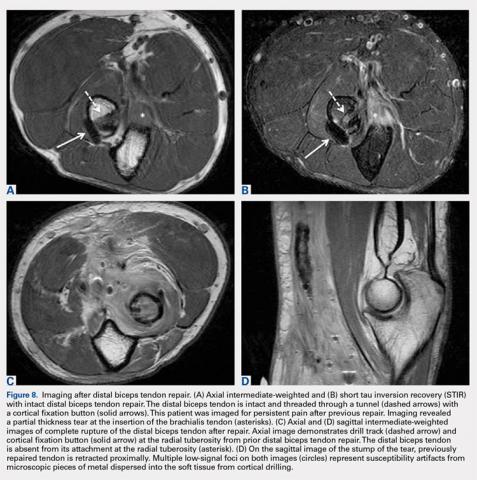

In distal biceps tendinosis, increased signals of thickened tendon fibers at the radial tuberosity are evident without focal discontinuity7,8 (Figures 6A-6C). Patients may display attenuation of the distal tendon fibers or adjacent fluid distension representing bicipitoradial bursitis (Figures 7A, 7B).MRI is useful in assessing the distal biceps tendon in the postoperative setting to evaluate the integrity of a repaired tendon. Cortical fixation button technique for repair creates minimal susceptibility artifacts on MRI. Postoperative MRI typically demonstrates a transverse hole drilled through the proximal radius at the site of the tuberosity with a cortical fixation button flush against the posterior radial cortex (Figures 8A-8D).

The postoperative complication of heterotopic ossification can occasionally be observed on plain radiograph at the site of surgery, but it is less common with the current surgical technique than in the past.11